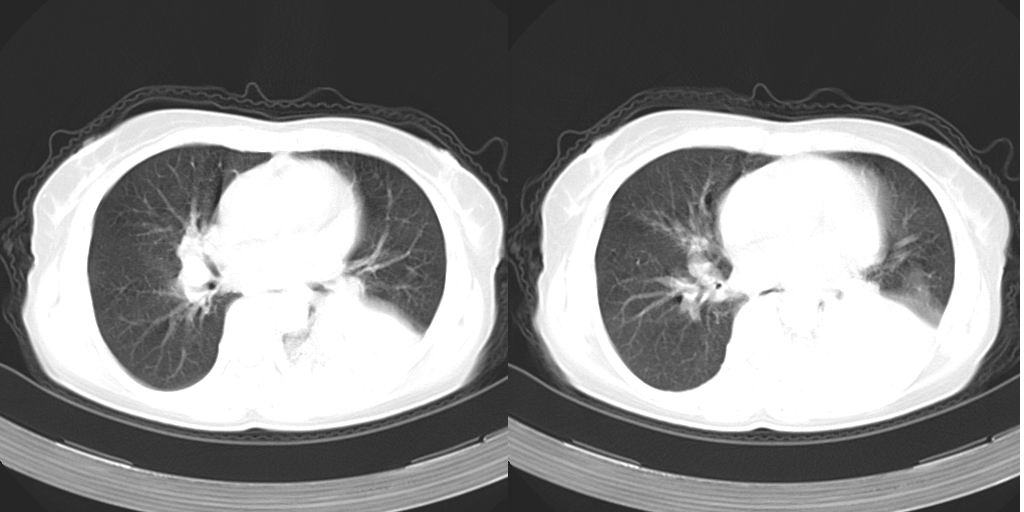

以下是引用dyqct在2007-1-23 15:01:00的发言:[br]左肺下叶实变、略萎陷,近肺门下部密度不均。上腔静脉后及隆突前见肿大淋巴结。余未见异常。[br]考虑:1、左肺下叶中心型肺癌伴肺不张、纵隔淋巴结转移;[br] 2、建议增强扫描并做任意平面重建确定肿块范围及支气管受累情况。

以下是引用同在2007-1-23 19:59:00的发言:[br]左肺下叶中央型肺癌伴肺不张及纵隔淋巴结转移.